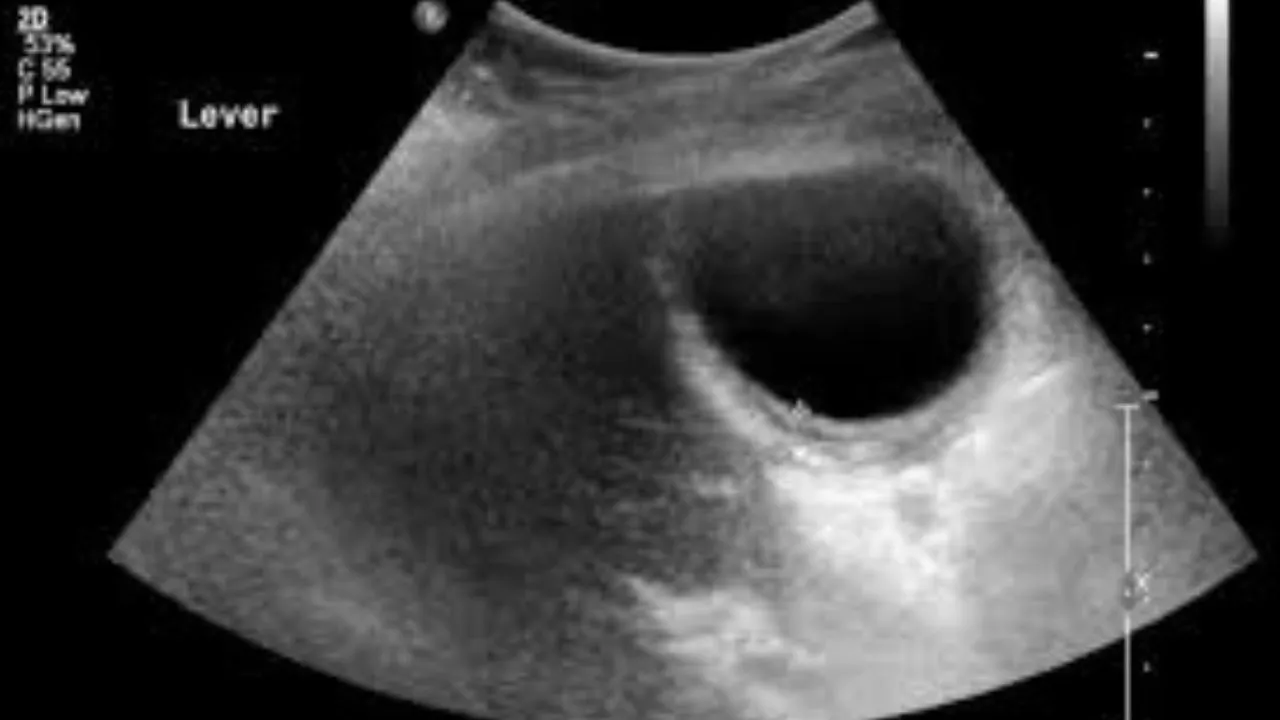

लखनऊ, वाईबीएन संवाददाता। अलीगंज स्थित चरक पैथोलॉजी की लापरवाही ने हर किसी को हैरान कर दिया है। जिस मरीज का ऑपरेशन नहीं हुआ, उसकी अल्ट्रासाउंड रिपोर्ट में बताया गया कि उसका गाल ब्लैडर (पित्त की थैली) गायब है। ऑपरेशन कर उसे निकाला जा चुका है। मरीज ने सीएमओ कार्यालय में शिकायत की है, जिसके बाद जांच के आदेश दिए गए हैं।

कल्याणपुर निवासी 42 वर्षीय प्रमोद मिश्र पेट दर्द की समस्या से पीड़ित थे। डॉक्टर ने मरीज को अल्ट्रासाउंड जांच लिखी। उन्होंने अलीगंज स्थित निजी डायग्नोस्टिक सेंटर में अल्ट्रासाउंड कराया। जांच फीस 1,160 रुपये जमा की। जांच रिपोर्ट अपने पर वह हैरान हो गए। रिपोर्ट में बताया गया कि ऑपरेशन के बाद उनका गाल ब्लैडर निकाला जा चुका है।

प्रमोद ने बताया कि पांच महीने पहले किडनी में पथरी का ऑपरेशन कराया था। उसके बाद कराए गए अल्ट्रासाउंड में गाल ब्लैडर था। प्रमोद का कहना है कि गाल ब्लैडर निकाले जाने की गलत रिपोर्ट थमाई गई है। पीड़ित ने निजी डायग्नोस्टिक सेंटर के खिलाफ सीएमओ कार्यालय में शिकायत दर्ज कराई। सीएमओ डॉ. एनबी सिंह का कहना है कि मामले की जांच के लिए कमेटी बनाई गई है। रिपोर्ट के आधार पर कार्रवाई होगी।